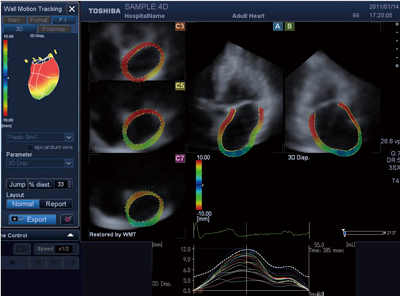

最新の3D WMTでは,前述のCRT応用における非同期の様子や,心筋虚血のサインとして知られているpost-systolic shorteningの分布を表現することを目的とした,strain等のピーク値到達時間をカラーコード化して表示する“Dyssynchrony Imaging(DI)”機能が追加されている。DI表示は,3D WMTの各種パラメータについての適用が可能となっている。図4に,Area TrackingによるDI表示例を示す。本健常例では,心尖部よりも心基部のピークが遅れている様子が確認される。

図4 Area TrackingによるDI表示例(健常例)